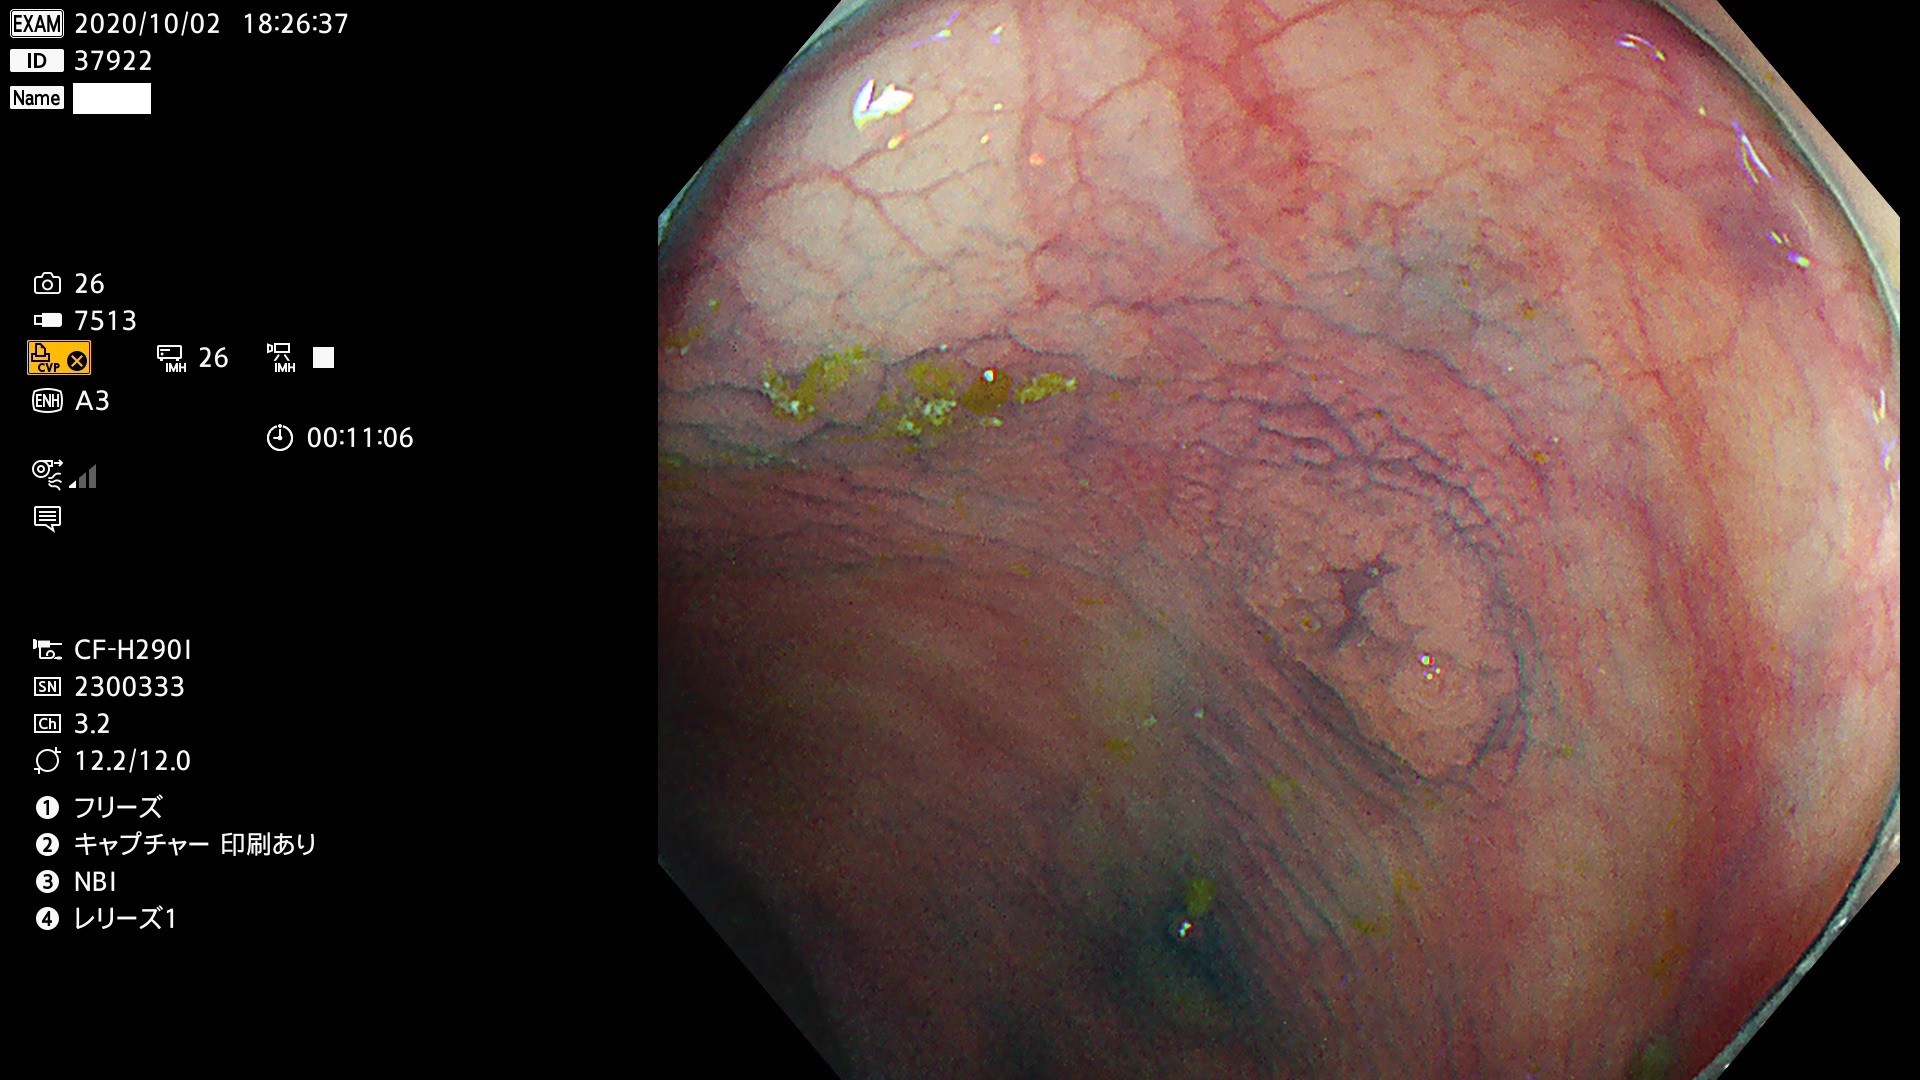

腺腫発見率 78  % (カルテ番号 37900〜37999の100名の方の検査結果で集計)

37900 37902 37903 37904 37905 37906 37907 37909 37910 37911 37912 37913 37914 37915 37916 37917 37919 37921 37922 37923 37926 37928 37929 37930 37931 37933 37934 37935 37936 37937 37938(SSAPのみ) 37939 37940 37941 37942 37943 37946 37947 37948 37949 37951 37952 37953(SSAPのみ) 37955 37956 37957(SSAPのみ) 37958(SSAPのみ) 37960 37962 37963 37964 37966 37967 37968 37971 37972 37973 37975 37976 37977 37979 37982 37983 37984 37985 37986 37987 37988 37989 37990 37991 37992 37993 37994 37995 37996 37998 37999

発見困難で危険性の高い平坦型病変(上記100名より抽出)